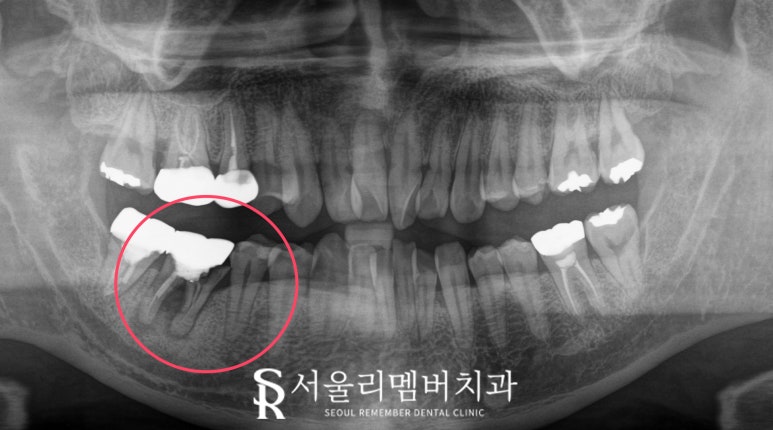

바로 뒷니인 첫 번째 큰 어금니(46번)는

뿌리가 부러졌습니다.

아무래도 음식을 먹는데

제일 중요한 역할을 하다 보니

힘을 많이 받았고,

주변 뼈가 녹으면서

염증이 생기다가

결국 금이 가고 부러지게 된 거 같네요.

이 정도면 잇몸도 많이 붓고

통증도 심하셨을 겁니다.

서울대입구역 치과 에서는

이렇게 치근 파절이 있을 경우

지체 없이 발치 후 임플란트를 하시길

권해드립니다.

치조골 안에서 부러진 뿌리를

다시 붙일 수 없고

그대로 두변 주변으로 감염 범위만

넓어질 것이기 때문이죠.